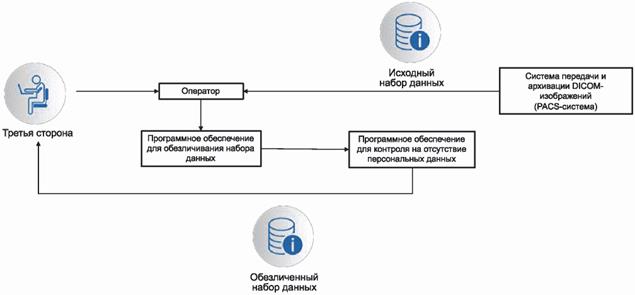

Возможная схема реализации процесса обезличивания набора данных при необходимости их передачи третьей стороне приведена на рисунке 1.

Рисунок 1 - Пример схемы процесса обезличивания набора данных при необходимости их передачи третьей стороне